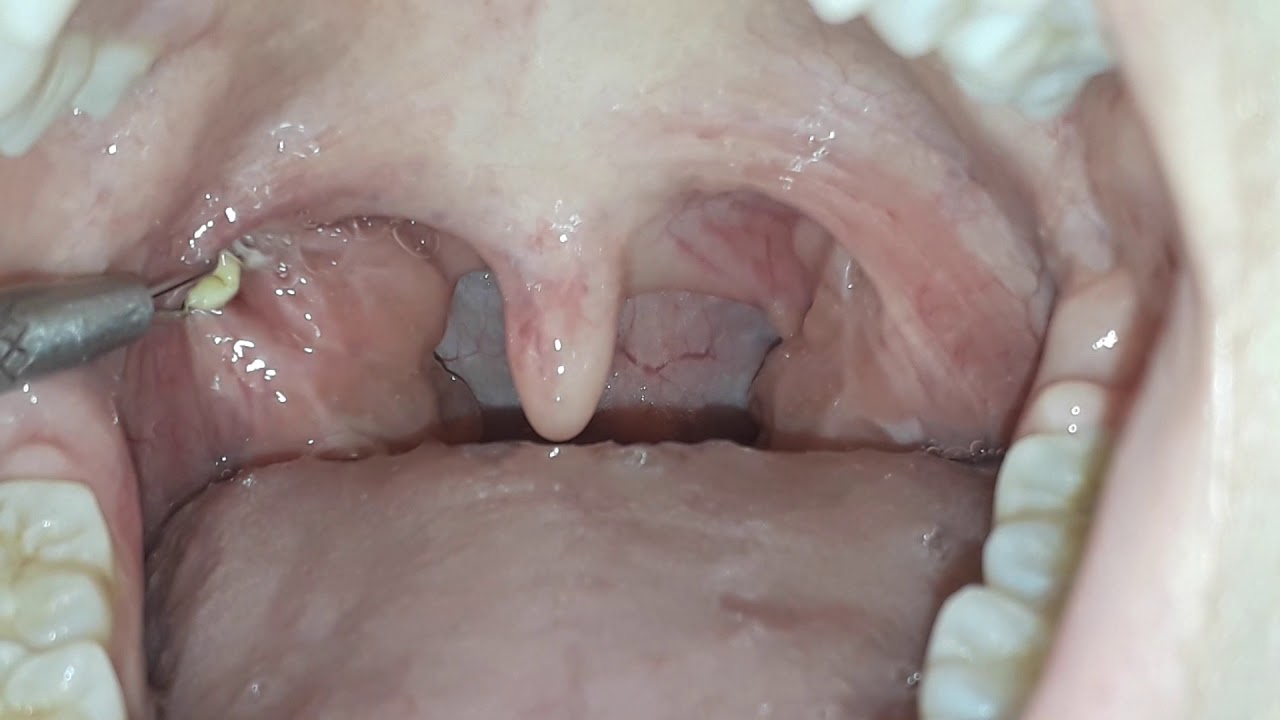

1000 Difficult Tonsil Stones removal 2021

Tonsil stone removal

Huge Tonsil Stones Removal in a case of Chronic Tonsillitis & Allergic